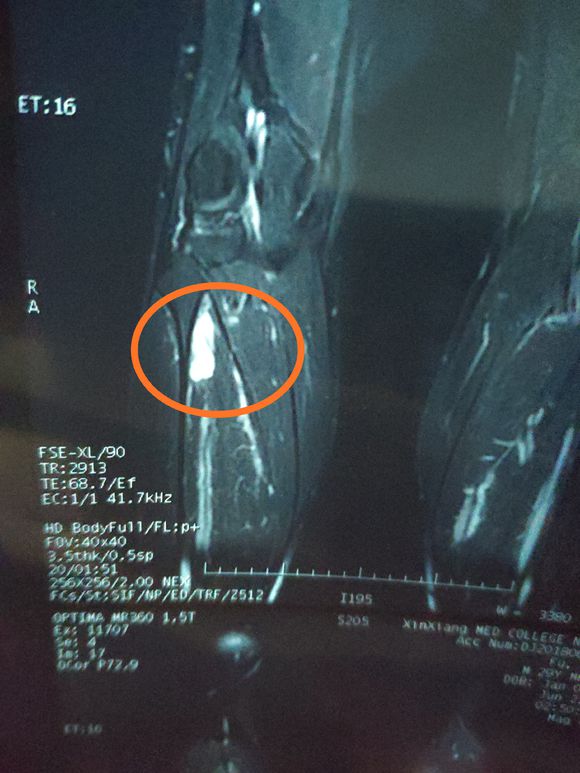

身心俱疲斗争 02019-02-22 患者家属女儿14岁,明天做截肢手术。医生让从髋关节处截,想保留个七八公分。问问大神们髋关节以下留七八公分能用常规的假肢吗? ...

一路向北 02019-01-28 患者家属我孩子今年15岁,年初查出骨肉瘤,左腿关节处,化疗5次做载肢,手术后伤口感染误了化疗,两个多月快三个月发生肺转,如今刚住...

X-man 02019-01-22 患者本人十九岁,九月十号因恶性骨肉瘤在云南省肿瘤医院做了截肢手术,后发现肺上有三个结节,一个大约一厘米,两个不足一厘米,请问...